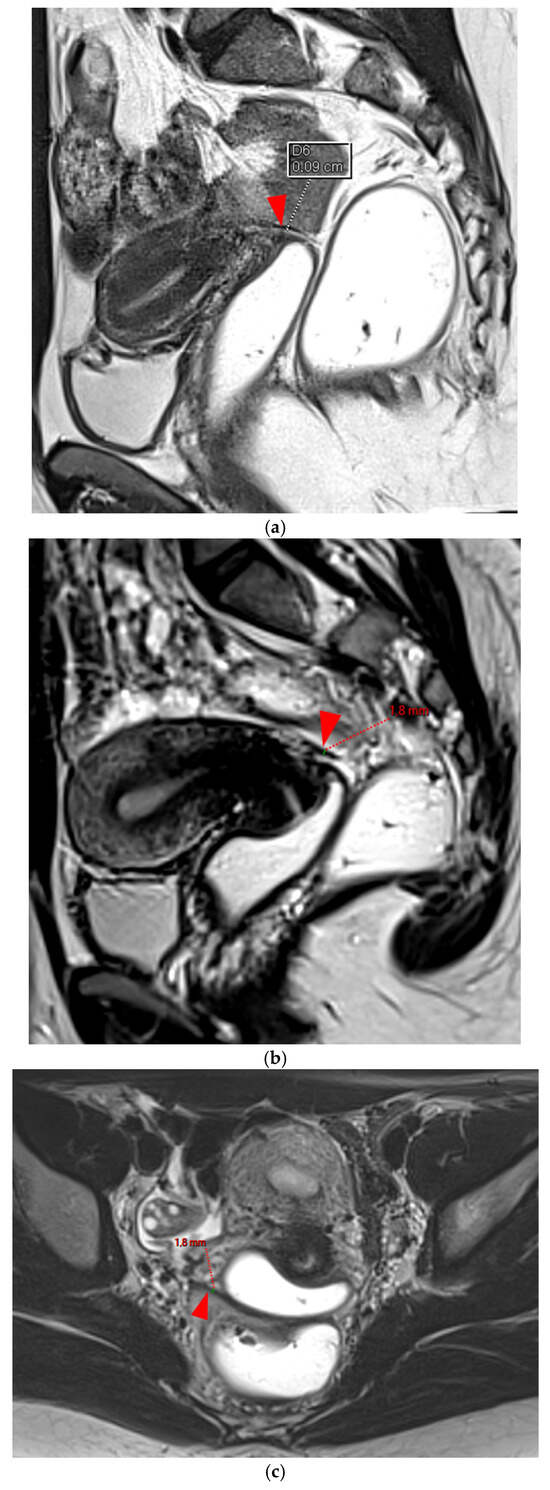

A type 6 USL is associated with adjacent pelvic “visceral” involvement in a broad sense. It most commonly affects the digestive tract (Figure 8 and Figure 9), with the rectum and rectosigmoid junction wall thickening: in this case, the lesion often appears as a “medallion-shaped” protrusion into the lumen. Less frequently, the urinary tract is affected (Figure 9 and Figure 10), involving the muscular layer of the bladder or even the distal ureter at the level of the common iliac artery, with stenosis potentially leading to upstream hydronephrosis. More rarely, as USLs are also close to nearby pelvic nerve structures (Figure 11), contiguous involvement of the inferior hypogastric plexus located in the sacro-recto-genital septum (a.k.a. Delbet sagittal fascia) beneath the distal two-thirds of the USL, or exceptional involvement of the sciatic nerve adjacent to the pelvic wall, is possible (Figure 12, Figure 13 and Figure 14).

Figure 9. Pelvic MRI scan of a patient with HTD type 6 USLs. (ad) Sagittal (a) and axial (b) T2WI, sagittal (c) and axial (d) contrast-enhanced T1WI demonstrate involvement of the posterior bladder wall (arrows) and rectal wall infiltration appearing as a “medallion-shaped” lesion (arrowheads). (e) Sagittal fat-suppressed T1WI shows two hyperintense hemorrhagic spots at the origin of the USLs (dashed arrows) and another within the bladder lesion (arrowhead). The presence of “visceral” involvement of both the digestive and urinary tracts results in reclassifying these type 4 USLs as type 6.

Figure 14. Pelvic MRI scan of a patient with a HTD type 6 USL. (a) Axial T2WI shows a visible but thin (1.6 mm) left USL (dashed arrow) and a thick (3.5 mm) but smooth right USL (arrowhead), initially classified as a type 2 left USL and a type 3A right USL. (b) Axial fat-suppressed T1WI reveals hyperintense hemorrhagic spots within the left sciatic nerve (arrow). (c) Axial T2WI demonstrates spiculated nodularity within the left sciatic nerve (arrow), leading to reclassification as type 6 left USL due to this so-called “visceral” nerve involvement. Note the neurogenic amyotrophy (red star) of the left piriformis and gluteal muscles, including the gluteus maximus, gluteus medius, and gluteus minimus.